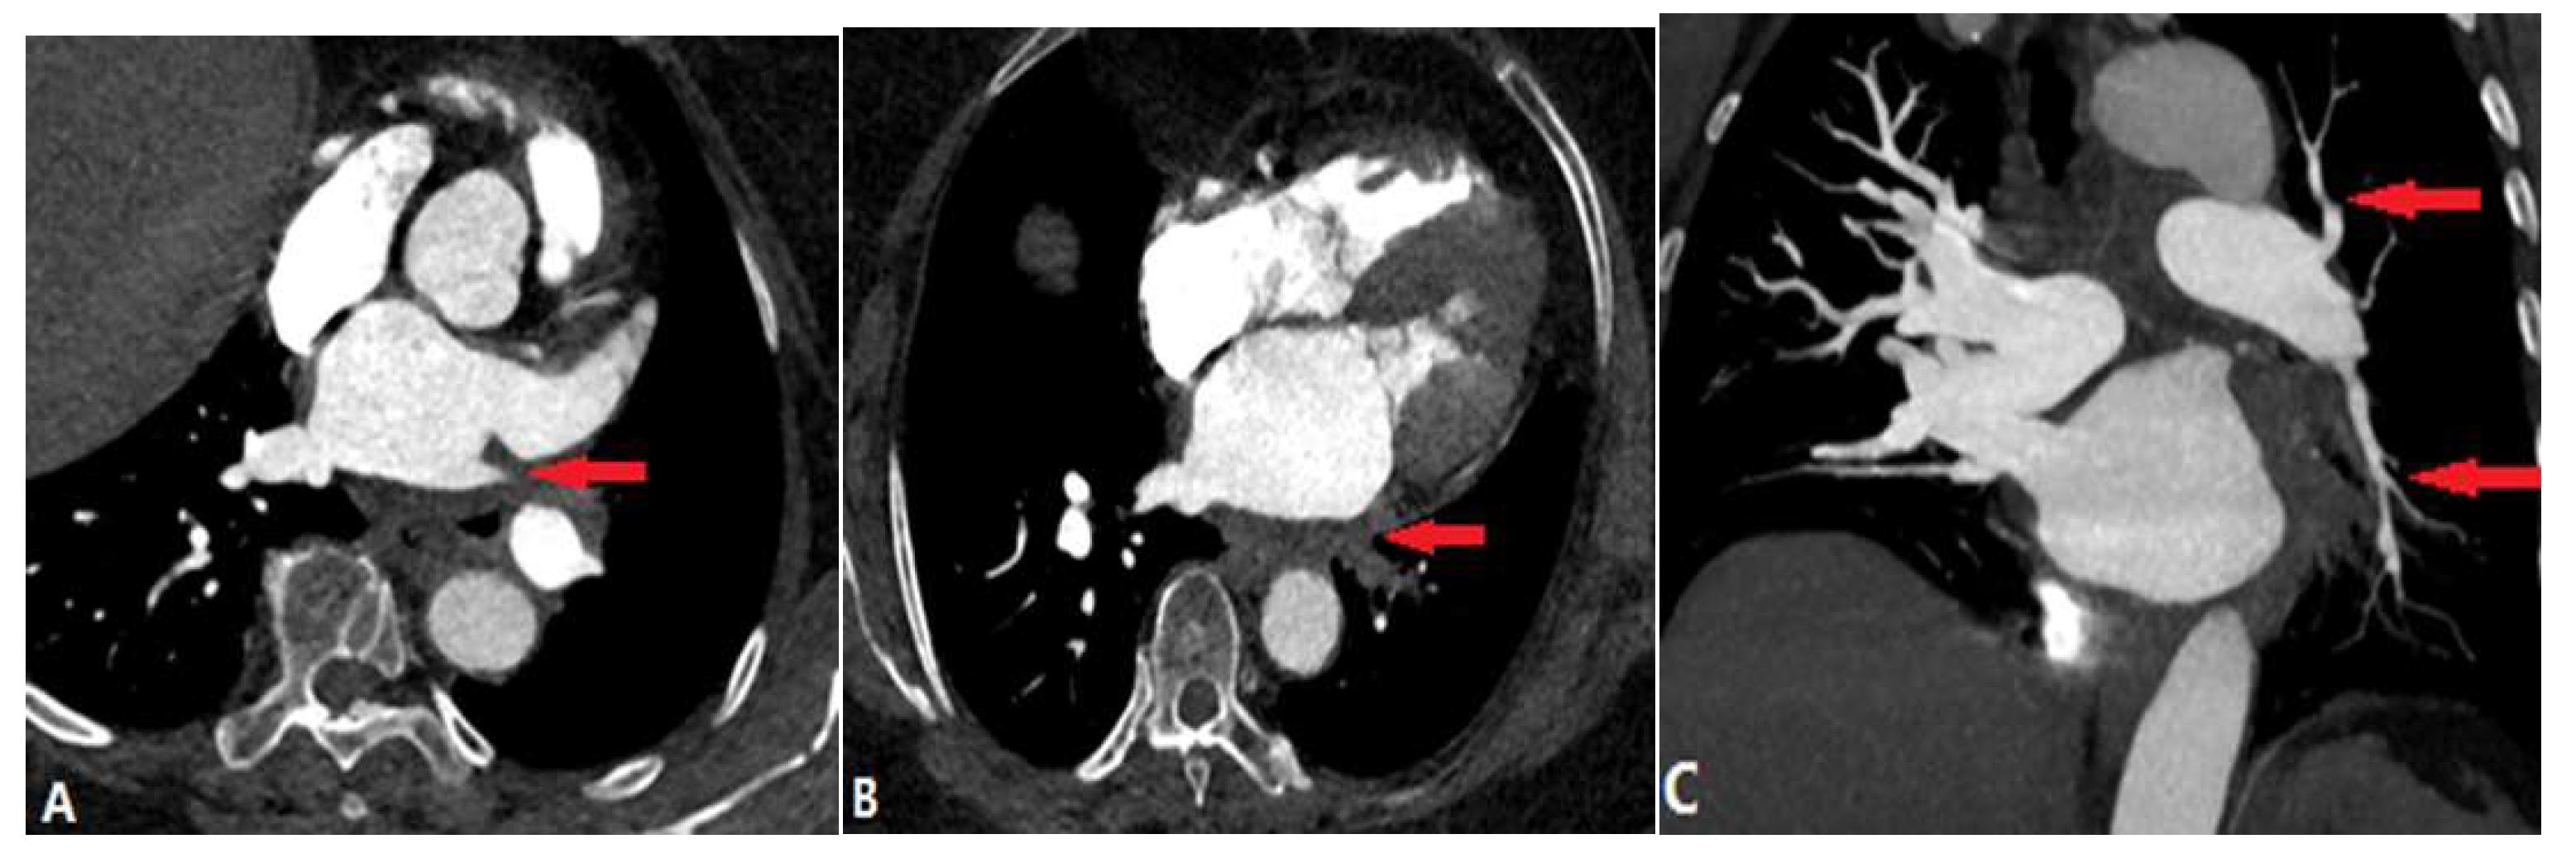

3.3. Extraluminal Abnormalities

3.3.1. Fibrosis Mediastinitis (FM)

3.3.2. Tumour Causing Pulmonary Artery Stenosis

3.3.3. Aortic Aneurysm